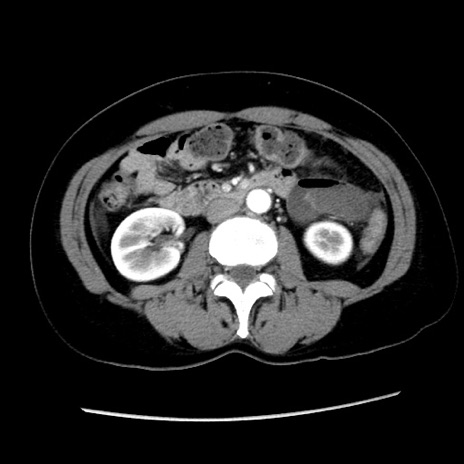

症例10(横断像)

【症例】 50歳代女性

【主訴】 腹痛

【現病歴】前日生レバーを食べた。今朝に排便あり。 昼前に突然発症の腹痛を生じ、当院救急外来を受診した。

【既往歴】 子宮筋腫にてで子宮全摘後

【身体所見】 意識清明、腹部:平坦、軟、下腹部やや左を中心に圧痛・反跳痛あり、筋性防御あり

【データ】WBC 7800、CRP 0.07